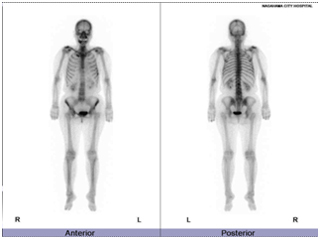

核医学装置

骨シンチ

脳血流SPECT

心筋SPECT